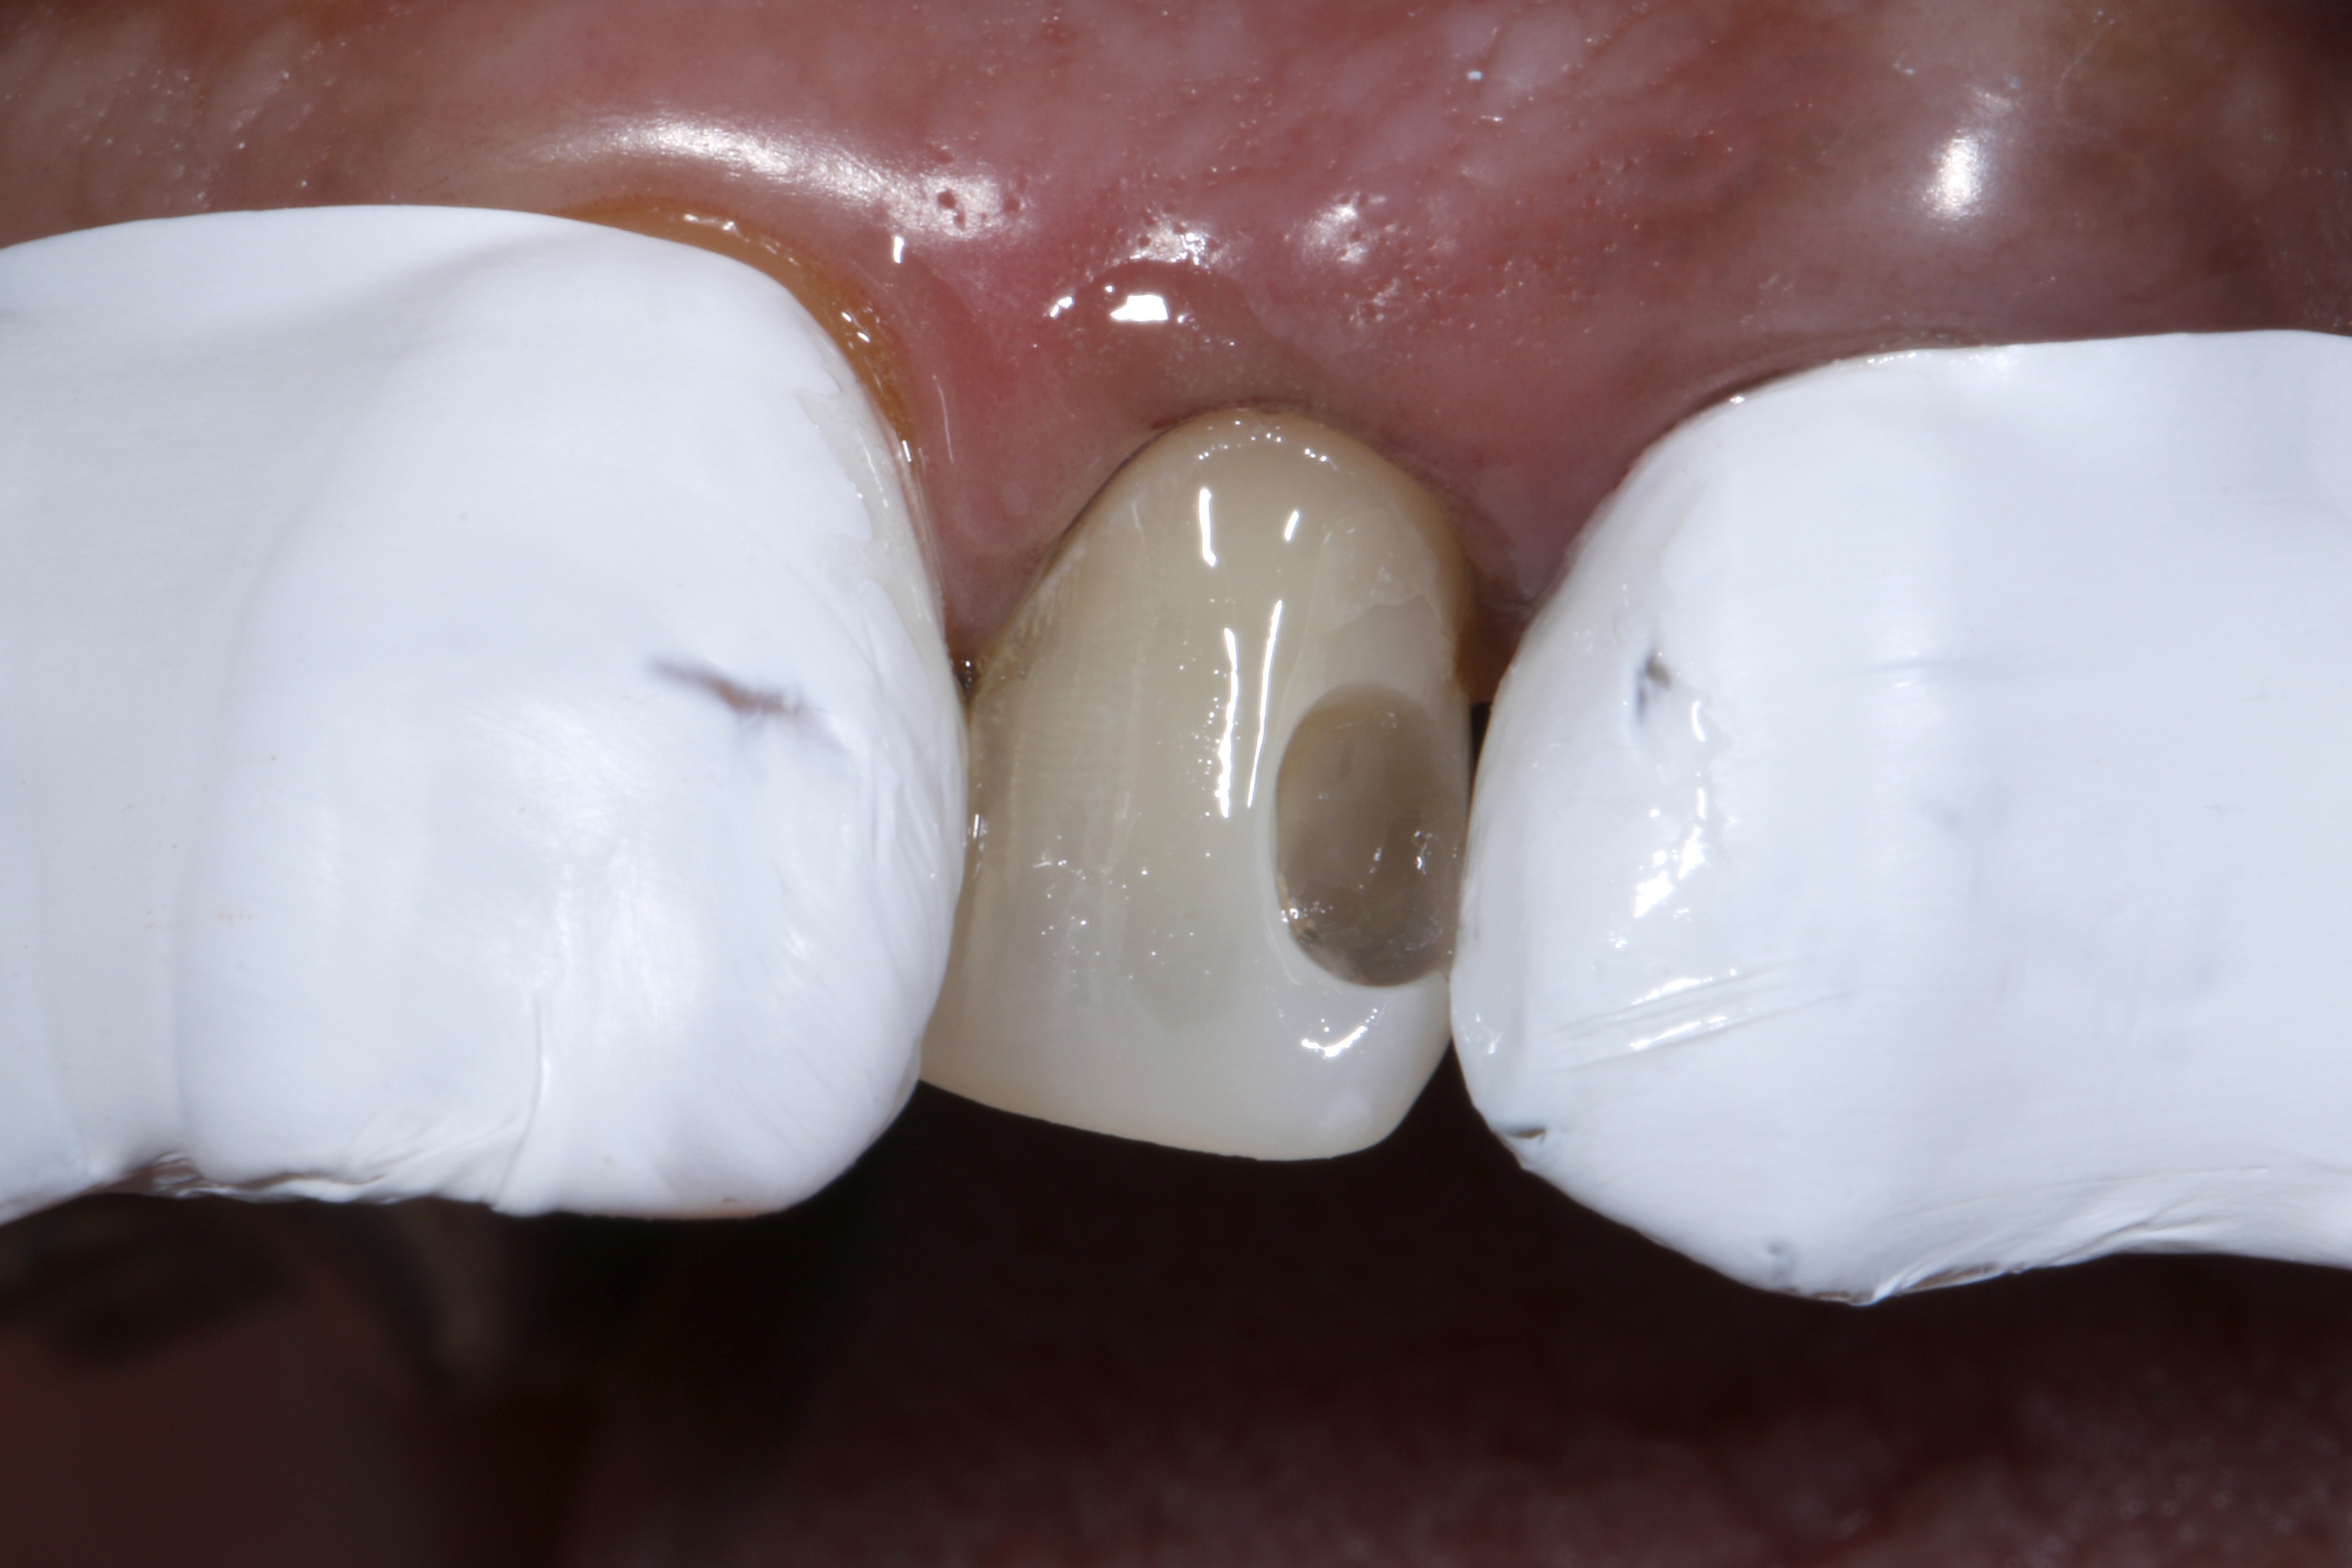

Leczenie rozpoczęto od dokładnego oczyszczenia zęba z zewnętrznych osadów za pomocą pasty profilaktycznej bez fluoru i gumki w kształcie kielicha. Następnie odpowiedni odcień kompozytu określono na wciąż wilgotnym zębie (ryc. 3).

Ryc. 3. Dobór odcienia na wilgotnym zębie

Wybrany odcień kompozytu sprawdzono, nakładając niewielką porcję kompozytu na powierzchnię zęba, który nie został wysuszony i nie był wstępnie zabezpieczony materiałem wiążącym (17). Konieczna jest polimeryzacja próbki kompozytu światłem przez czas określony przez producenta w celu uzyskania miarodajnego porównania optycznego. Dopiero przy wystarczającej ekspozycji na światło fotoinicjator kamforochinon, który jest zawarty w większości kompozytów i ma intensywnie żółty kolor, ulega w dużej mierze zużyciu i przekształceniu w bezbarwny produkt reakcji („fotowybielacz”) (18–23). Po polimeryzacji próbki kompozytu nałożonej na powierzchnię zęba, jej właściwości optyczne porównano z otaczającą zęba substancją pod względem odcienia i stopnia przezierności. Na tym etapie można łatwo dokonać korekty, zastępując niedopasowaną optycznie próbkę materiałem kompozytowym o zoptymalizowanym odcieniu. Ten indywidualny proces weryfikacji, który zajmuje bardzo mało czasu, gwarantuje, że do kolejnej odbudowy zostanie użyty optymalnie dopasowany materiał kompozytowy. Oznacza to, że w niemal wszystkich przypadkach można uniknąć czasochłonnych poprawek, a nawet nowych wypełnień z powodu skarg pacjentów na estetykę.